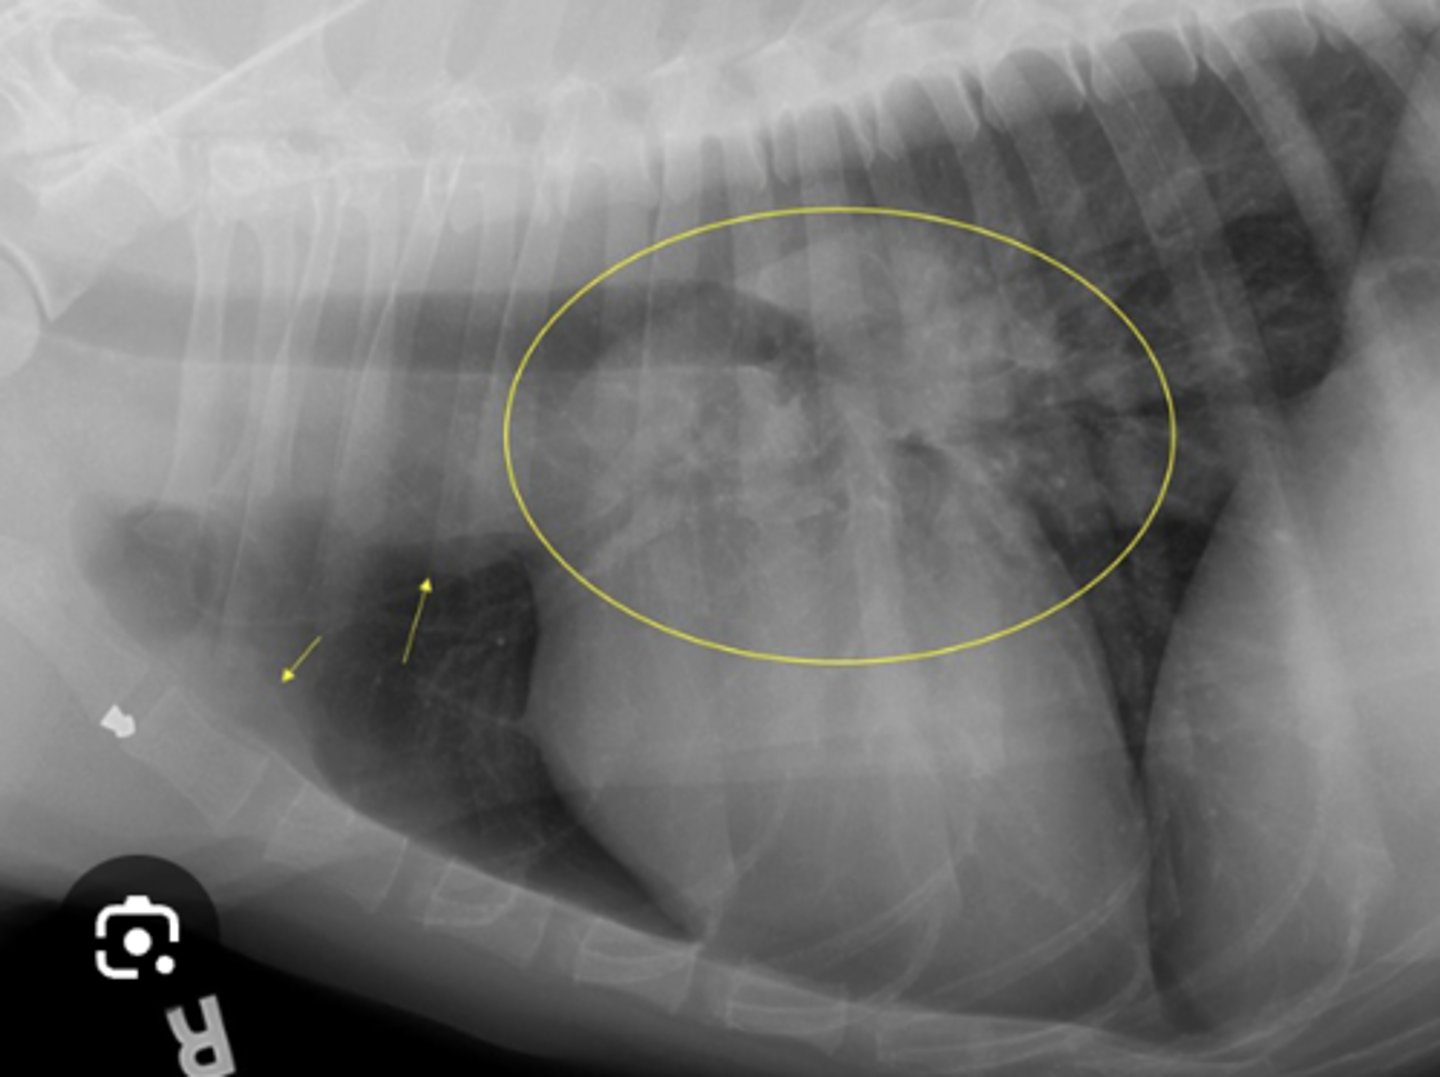

GDV

10 yo lab with abdominal distention, panting- what has caused this?